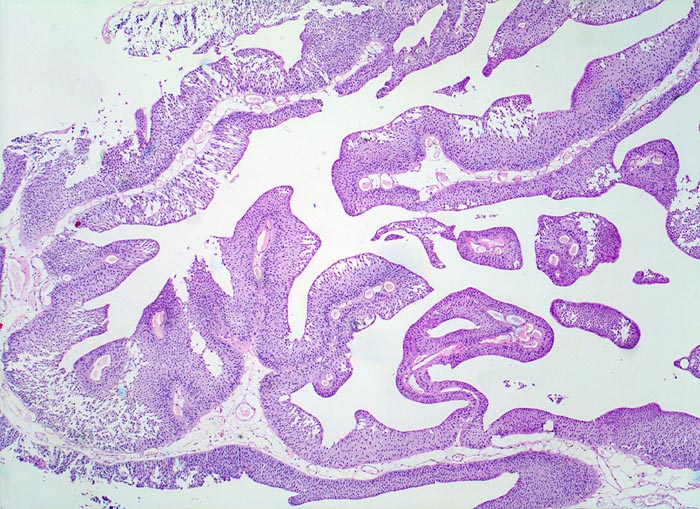

PathoPic – image database / PathoPic ID 5046 - Nicht invasives papilläres Urothelkarzinom pTa

Nicht invasives papilläres Urothelkarzinom pTa

Lockeres fibrovaskuläres Stroma wird bedeckt von einem verbreiterten Urothel. Eine durchgehende Basalmembran ist erkennbar. Das Stroma wird nicht infiltriert.

Die zystoskopische Abklärung einer Makrohämaturie ergab einen papillären Tumor an der Blasenhinterwand. Der Tumor wird transurethral reseziert.

pTa Tumoren stellen nicht invasive Tumoren dar. Trotzdem werden sie in der WHO Klassifikation als papilläre Karzinome bezeichnet (der Begriff Karzinom sonst ausschliesslich auf invasive epitheliale Tumoren mit metastatischer Potenz angewendet).